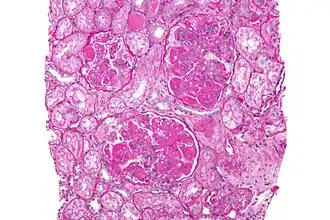

Микрофотография диффузного пролиферативного волчаночного нефрита: увеличение мезангиального матрикса и мезангиальная гиперклеточность. Биопсия почки. PAS окраска. | |